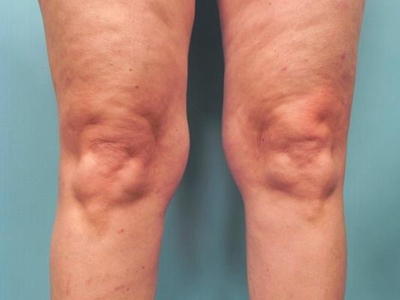

膝关节骨质增生症状图片

4、关节反复肿胀:积液多于不严重的外伤或轻度扭伤后引起关节肿胀积液,疼痛,关节周围压痛,膝关节肌肉痉挛。休息1-2个月后症状可自然消退,可以很长时间没有症状,但可因轻微外伤而反复发作,由于股四头肌无力或因疼痛,膝关节可出现“闪失”现象。

5、关节畸形:病情逐步发展,膝关节出现内翻或外翻畸形,关节骨缘增大。关节主动及被动活动范围逐步减小,关节疼痛转重,在走平路及站立时也引起疼痛感。关节韧带松弛出现关节不稳感,有些病人不能完全伸直膝关节,严重者则膝关节呈屈曲挛缩畸形。开始活动时疼痛加重,休息后缓解,以后可变为持续性疼痛。